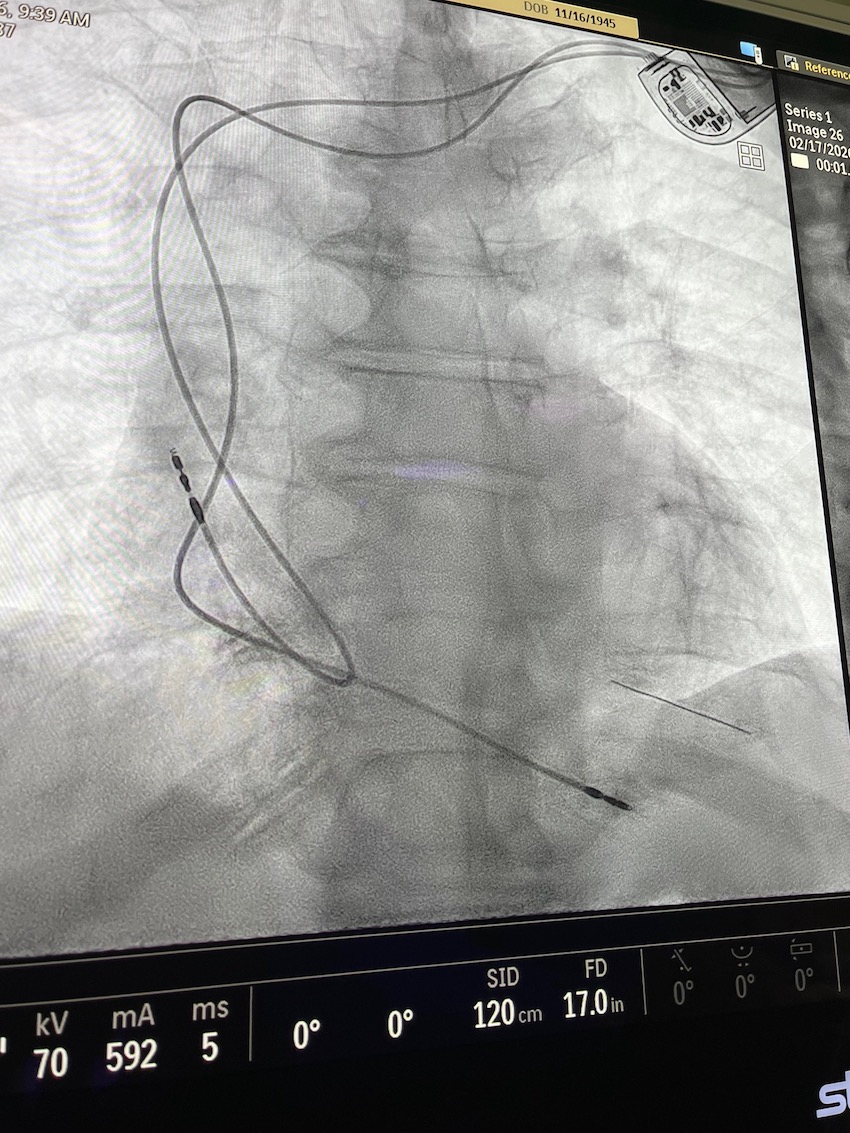

While the brief ceremony was taking place this morning in the Health First Viera Hospital lobby, the lab’s first patient, Malcolm Brand of Merritt Island, was being prepped just one floor above for his 35-minute procedure to implant a dual-chamber pacemaker.

Brand was scheduled to receive a dual-chamber pacemaker for a very slow heart rhythm that would dip below 40 beats per-minute – otherwise known as Bradycardia. After visiting with Campbell, he was fitted with a monitoring device to measure his heart performance over 30 days, and upon returning, Campbell informed him of the next steps.